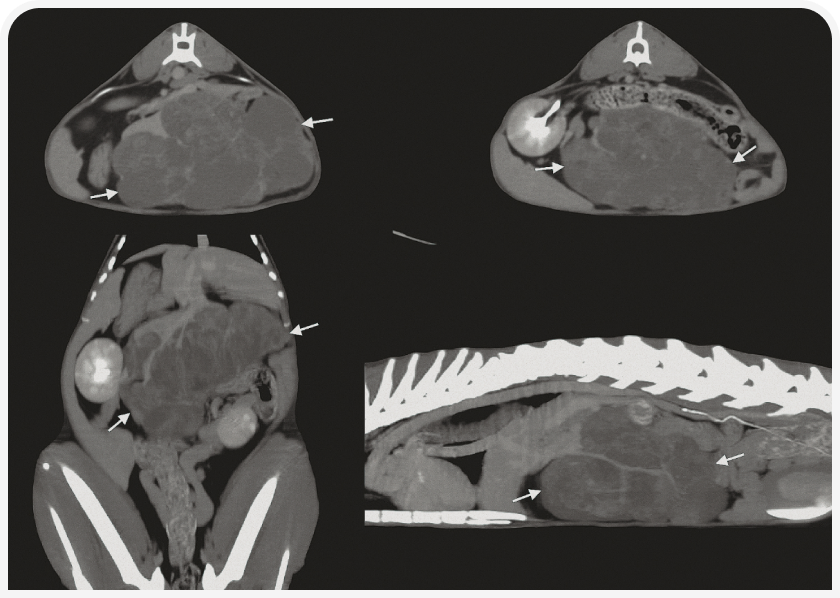

В норме структура печени однородная, сигнал ослаблен в степени, типичной для мягких тканей. КТ особенно рекомендуется для оценки точного местоположения и возможной диссеминации образования в печени в случае, если планируется хирургическое вмешательство (Рисунок 5). Также очень полезно оценить аномалии строения сосудов, особенно портосистемные шунты (внутри- или внепеченочные); в этом случае требуется провести визуализацию после инъекций контрастного вещества в трех временных точках: во время артериальной, портальной и венозной фаз (2).